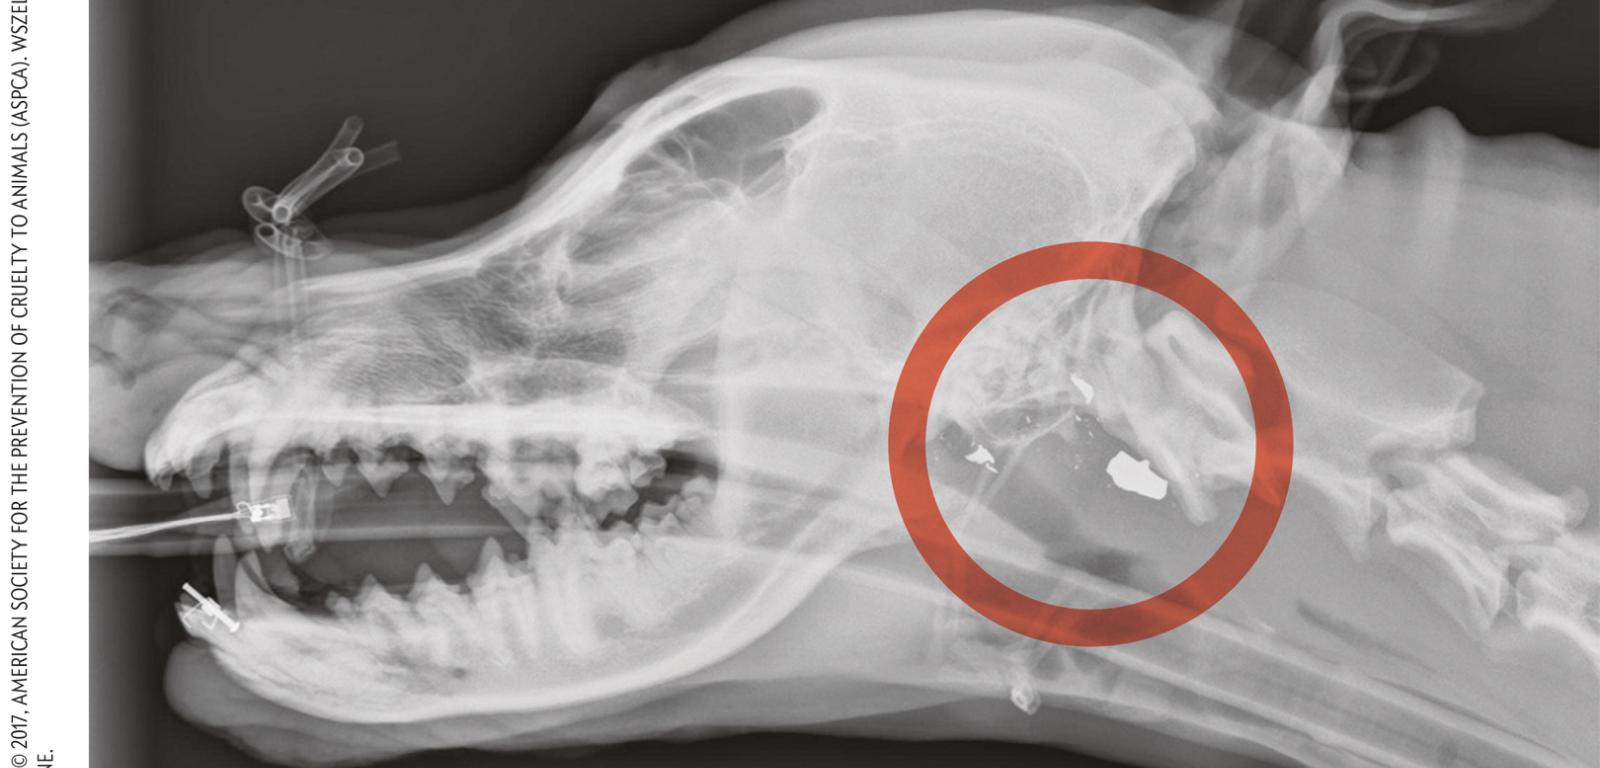

Analiza fragmentów pocisku (białe odłamki) tkwiącego w podstawie czaszki Honey (1) pomogła oskarżyć mężczyznę z Nowego Jorku o strzelenie zwierzęciu w otwarty pysk i stosowanie przemocy wobec właścicielki psa Ashy Stringfield (2). Analiza fragmentów pocisku (białe odłamki) tkwiącego w podstawie czaszki Honey (1) pomogła oskarżyć mężczyznę z Nowego Jorku o strzelenie zwierzęciu w otwarty pysk i stosowanie przemocy wobec właścicielki psa Ashy Stringfield (2).